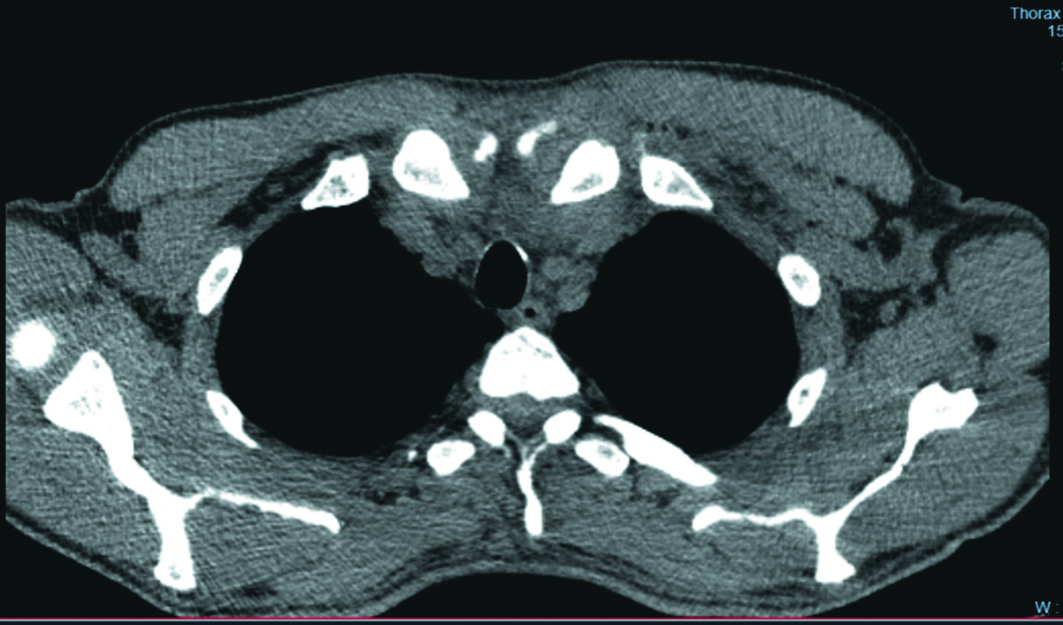

Пациент Л., 56 лет, поступил в гнойное хирургическое отделение ГБУЗ «Самарская городская клиническая больница №1 им. Н.И. Пирогова» 15.09.2022 г. в экстренном порядке с жалобами на боль в области левой ключицы и нарастающую слабость в левой руке. Болен в течение четырех суток. Страдает сахарным диабетом 2 типа на протяжении 10 лет, течение заболевания без осложнений, получает инсулинотерапию препаратами длинного и короткого действия. Первоначально 13.09.2022 г. был госпитализирован в неврологическое отделение с подозрением на острое нарушение мозгового кровообращения. Этот диагноз был исключен. На фоне проводимого лечения на протяжении двух суток боль в области левой ключицы не уменьшалась, появилась лихорадка до 37,7°С. При поступлении состояние средней тяжести. Определяется отек в области левого ГКС, сглаженность яремной вырезки, незначительная гиперемия кожи, локальная боль и гипертермия. На компьютерных томограммах выявлена инфильтрация тканей области левого ГКС, жидкость и воздух вокруг грудинного конца левой ключицы (рисунок 1).

Рисунок 1. Компьютерная томограмма груди. В области левого грудинно-ключичного сочленения определяются жидкость и воздух.